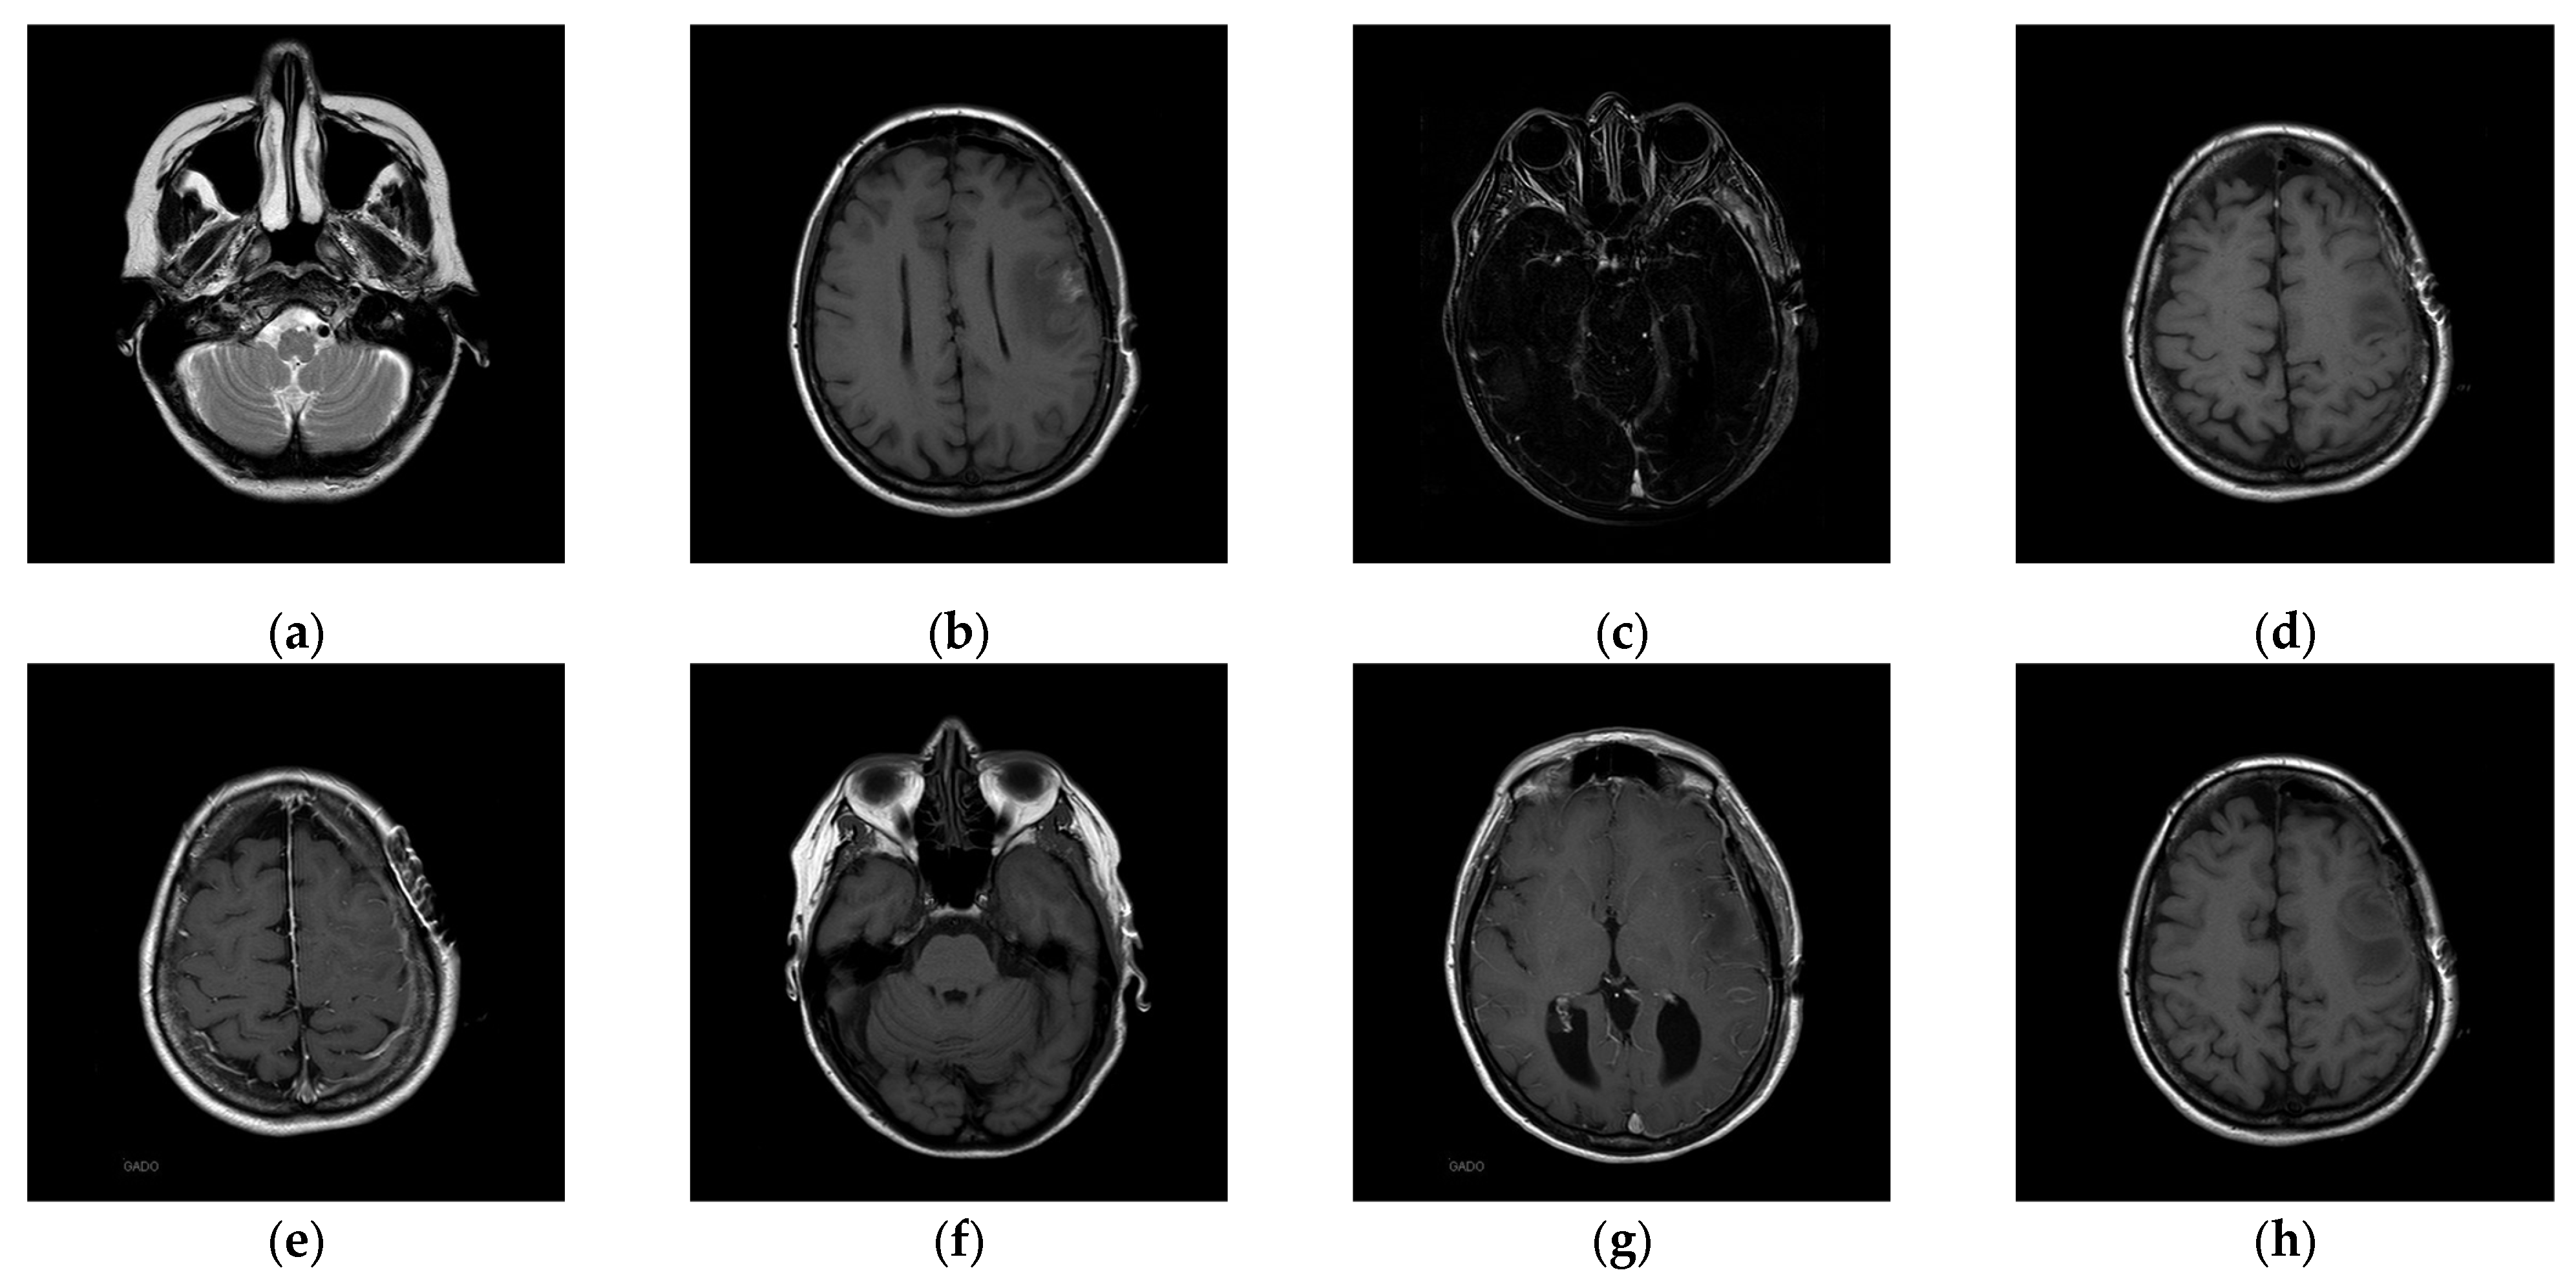

The experiments were conducted on two systems. The first system ran on Ubuntu 22.04, equipped with an Intel i7-9700KF CPU @ 3.60GHz (8 cores), an Nvidia GeForce RTX 3090 GPU, 32 GB of RAM, and Pytorch (https://pytorch.org/) for the experimentation. The second system, called the Type 1 device, is a notebook with an Intel(R) Core (TM) i7-10510U CPU @1.80 GHz 2.30 GHz, 16.0 GB RAM, 64-bit Windows operation system, and GPU MX 250. The third system, called the Type 2 device, is a notebook with an 11th Gen Intel(R) Core(TM) i5-11400H @ 2.70 GHz 2.69 GHz, 24.0 GB RAM, 64-bit Windows operation system, and GPU Nvidia GeForce 3060. The second system is a notebook that was released around 2019 or early 2020. The third system is also a notebook that was released in early 2021. The two systems were used to simulate resource-constrained environments. Different medical and test images were used as the test images to evaluate the performance of our proposed scheme and to make comparisons between our scheme and Qin et al.’s scheme [20]. In the first experiment, eight medical images, which are MRI scans of the brain, were randomly selected from the Osirix database [21] as test images and are presented in Figure 10 to demonstrate the performance of our proposed scheme in detail. In the second experiment, one hundred medical images, which are also MRI scans of the brain, were randomly selected from the Osirix database [21] to form Dataset 1 and Dataset 2, as shown in Figure 11, to prove the stable performance of our proposed scheme. In the third experiment, six general grayscale images, sized 512 × 512, demonstrated in Figure 12, were used to compare with those offered by Qin et al.’s scheme [20]. The logo depicted in Figure 13a was used as the watermark for the first and the second experiments and Figure 13b was used as the watermark for the third experiment.

Figure 10.

Eight medical test images. (a) 10.png; (b) 11.png; (c) 14.png; (d) 16.png; (e) 19.png; (f) 26.png; (g) 31.png; (h) 57.png.